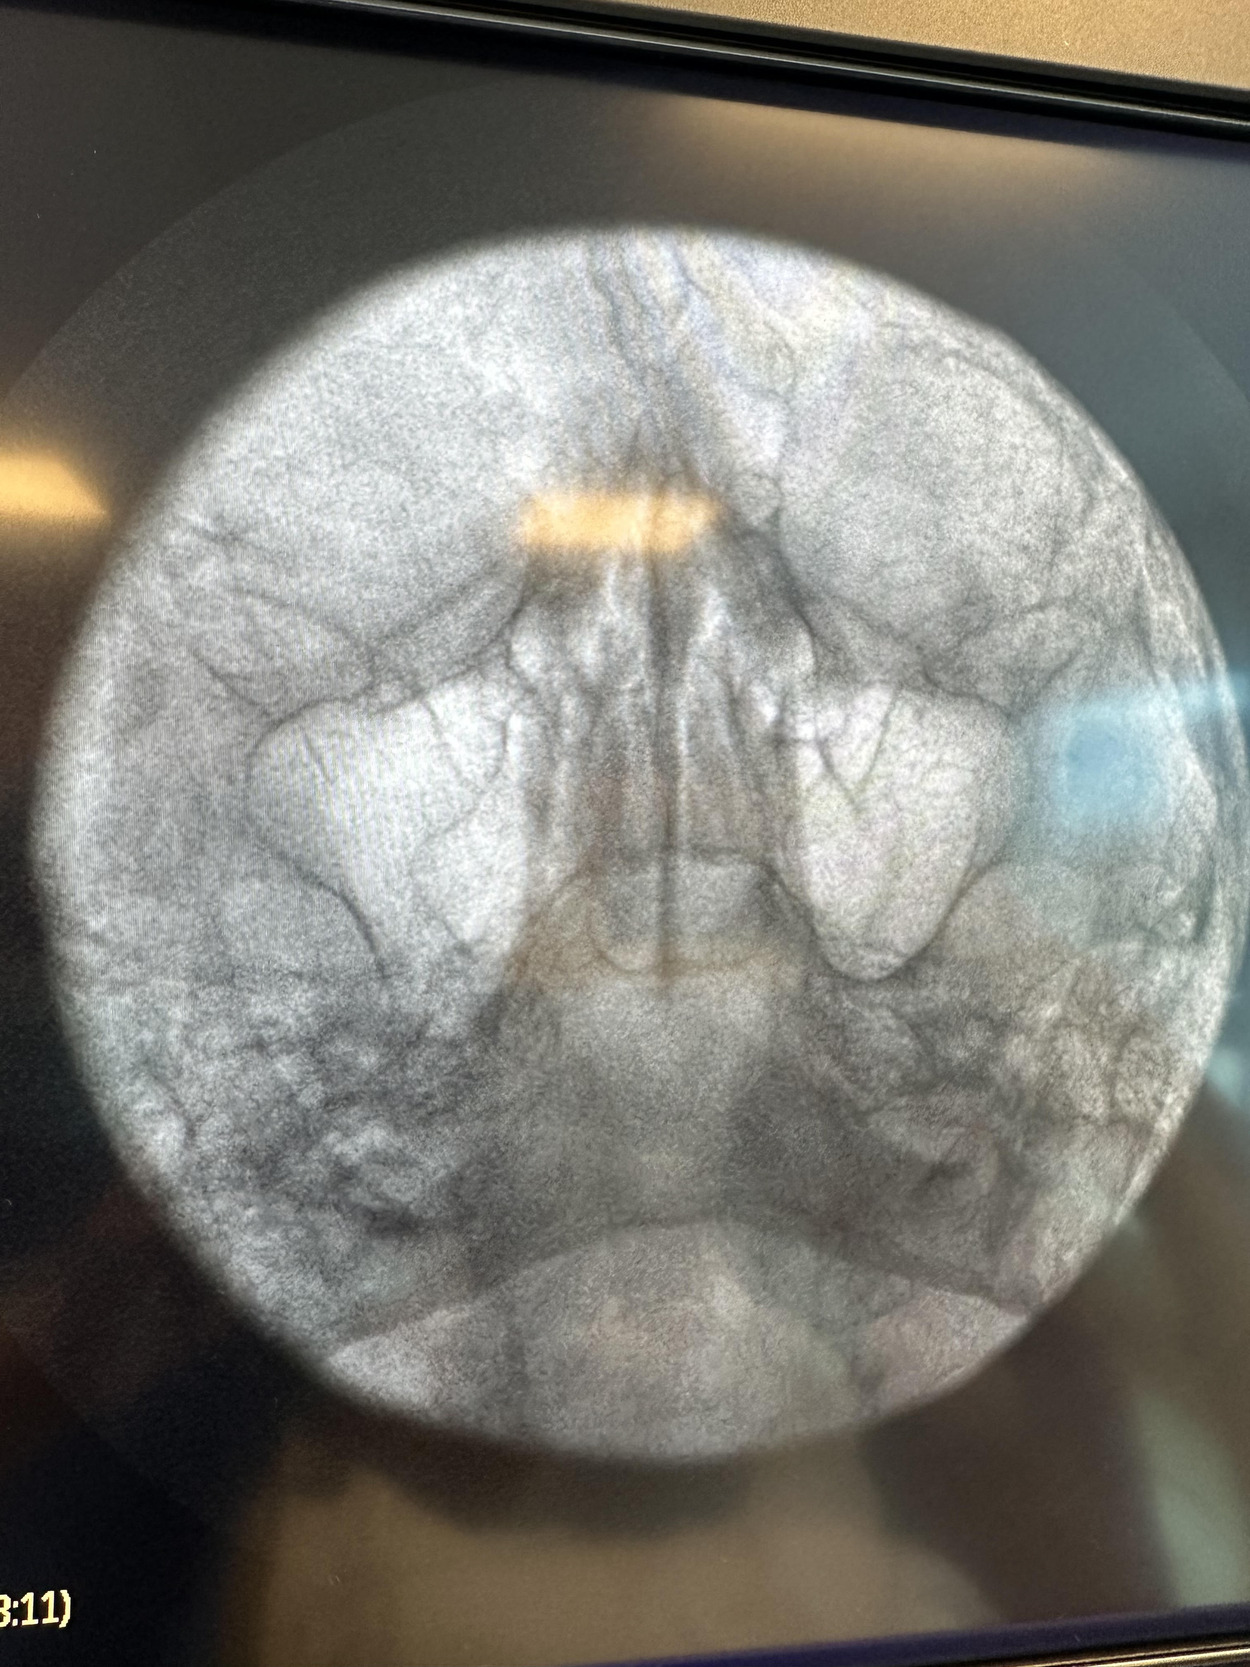

Given the patient’s refractory symptoms, medication intolerance, and elevated surgical risk, percutaneous cryoneurolysis was recommended. In April 2024, cryoneurolysis was performed at the ipsilateral foramen ovale targeting the V2 and V3 branches of the trigeminal nerve using a handheld cryotherapy device (iovera°, Pacira BioSciences, Inc., Brisbane, CA, USA). The procedure was performed under fluoroscopic guidance to confirm probe depth and alignment with the foramen ovale (Figures 1 and 2), and the patient tolerated the procedure well with no complications.